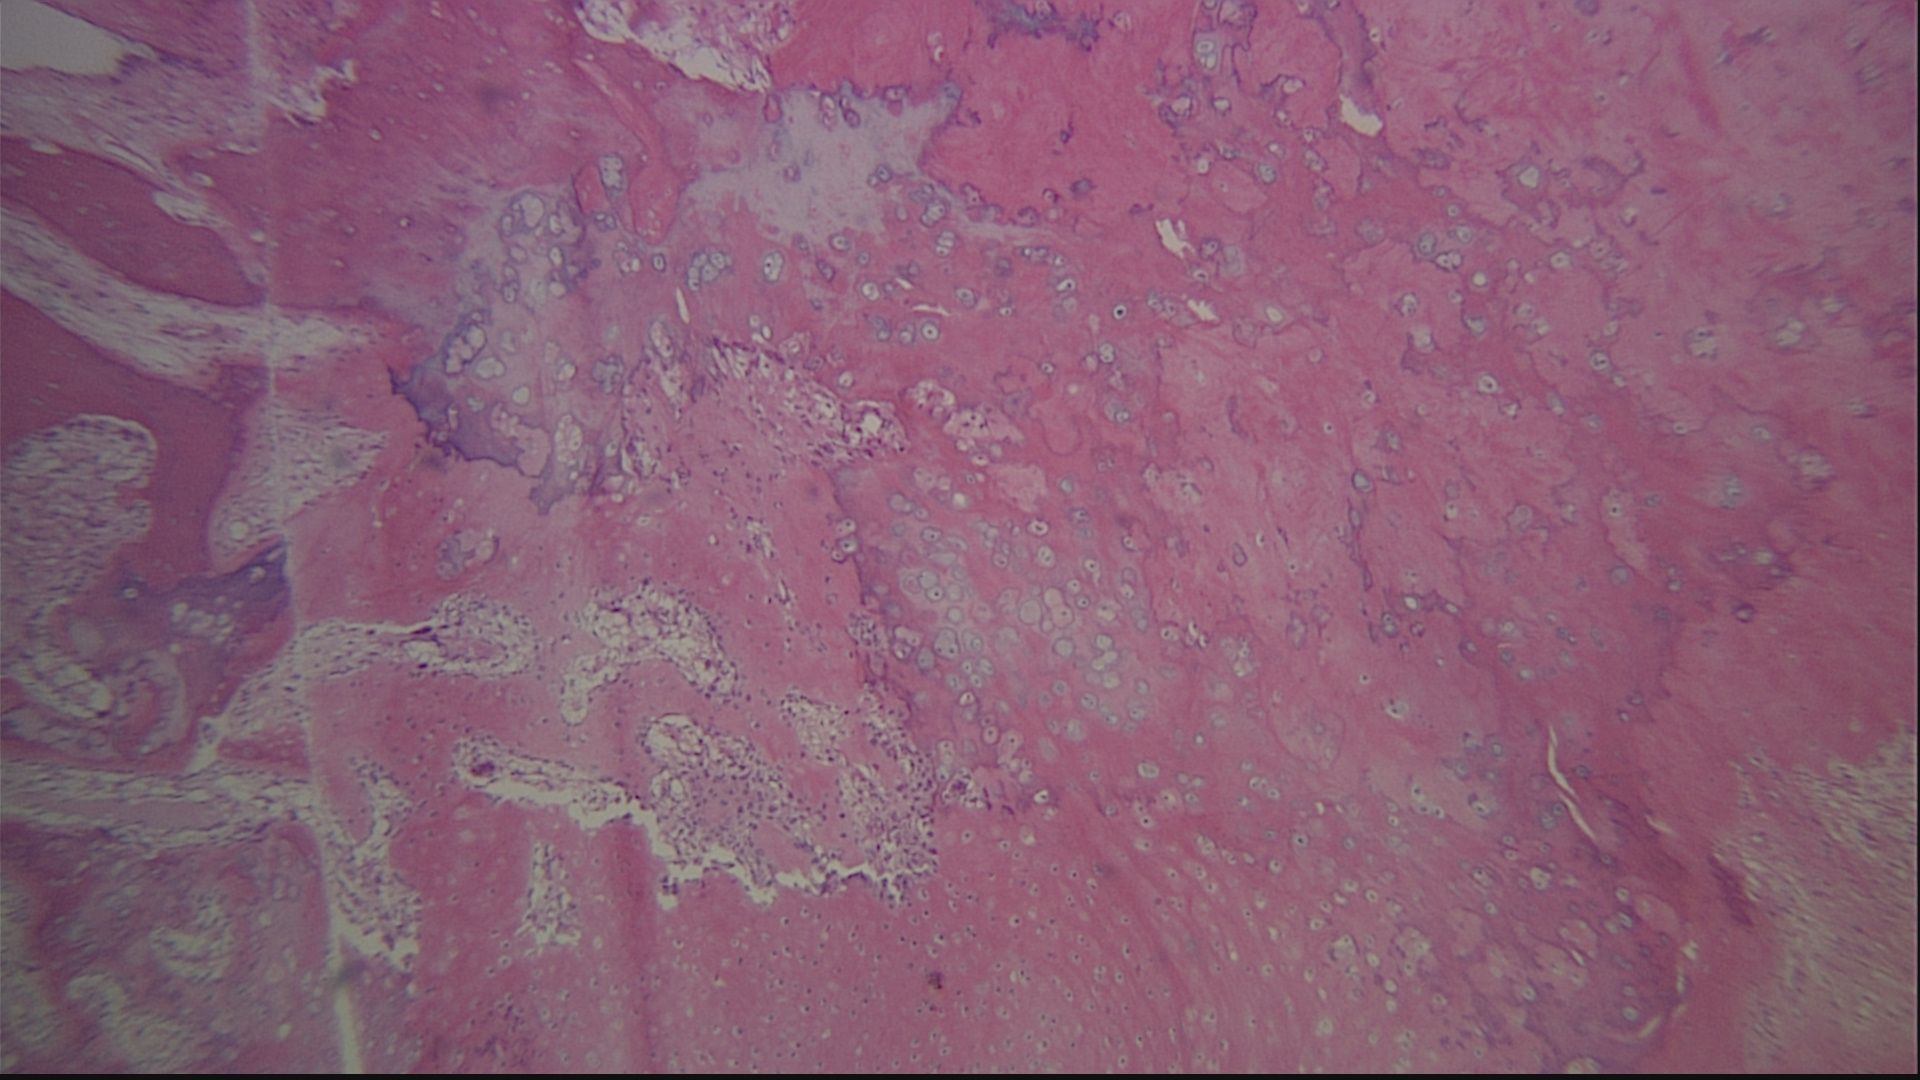

Figure 1 Preoperative medial oblique (A) and lateral (B) radiographic views demonstrating a radiopaque mass of the plantar midfoot with no bony involvement.

Figure 7 Histomicrograph showing benign chondrocytes adjacent to and admixed with bony spicules. The islands of benign chondrocytes in an area that usually does not have cartilage consitute a chondroma (original magnification 40x, hematoxylin and eosin).

Figure 8 Histomicrograph which shows the chondrocytes more clearly (high power magnification 100x, hematoxylin and eosin).